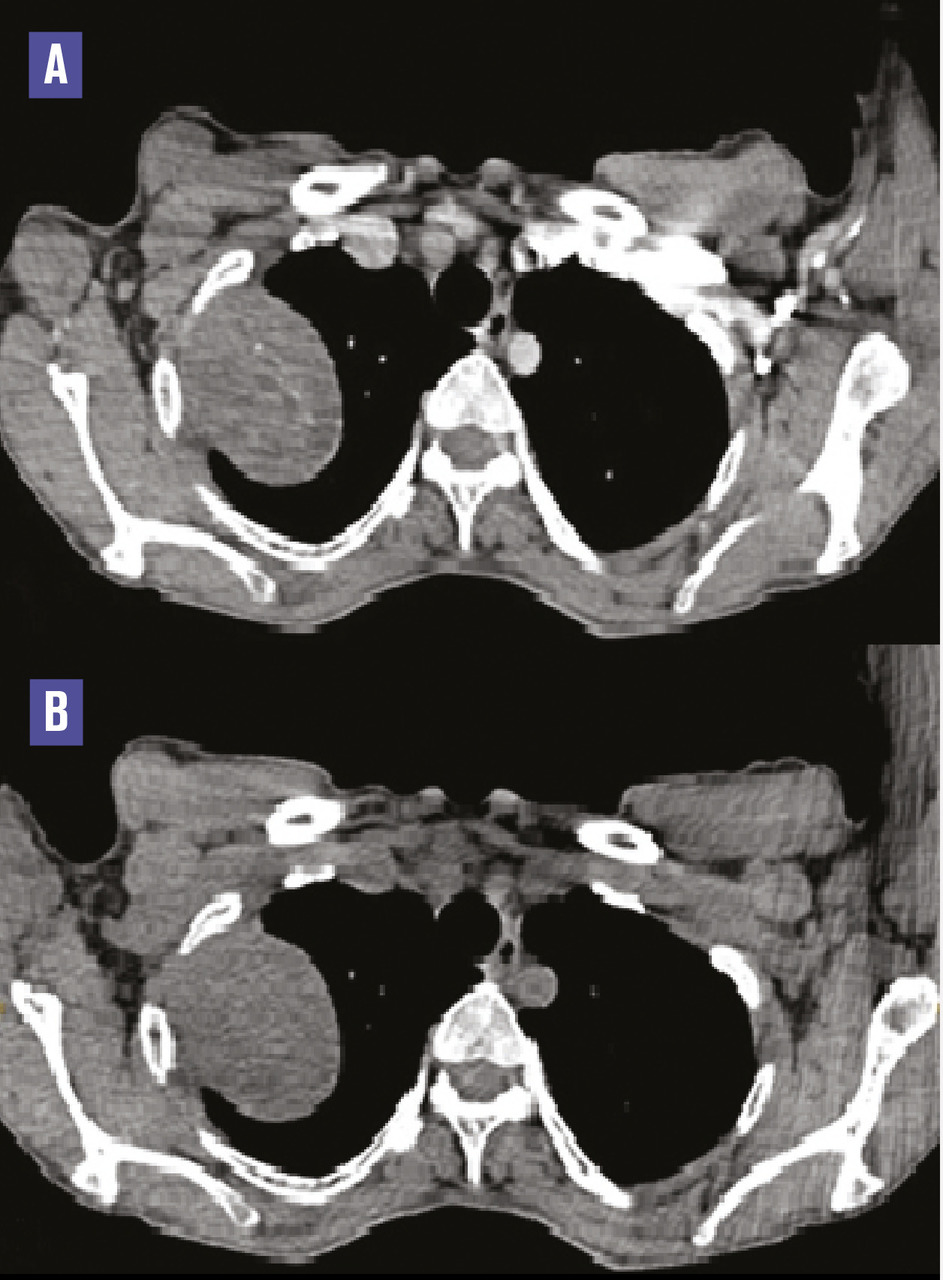

Cette femme de 44 ans était admise aux urgences pour une douleur thoracique aiguë et une dyspnée. La radiographie thoracique montrait une volumineuse opacité du tiers supérieur du poumon droit. La tomodensitométrie (TDM) sans et avec contraste (fig. 1 ) notait une masse bien limitée, de 60 x 46 x 45 mm, tissulaire homogène, faiblement réhaussée, avec une interface nette avec le poumon et un angle avec la 2e côte. L’origine pleurale était évoquée. Une biopsie scannoguidée permettait une analyse histologique en faveur d’un schwannome pleural bénin. En raison de l’aggravation de la dyspnée, une ablation chirurgicale était réalisée : la masse d’implantation pleurale respectait le parenchyme pulmonaire (fig. 2 ).